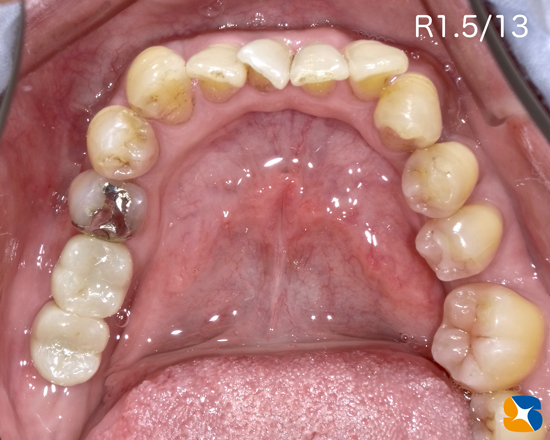

Before

型取り前

昨年、市内より40代の男性。主訴は「数年前、歯周病が原因で奥歯がぐらついて抜歯をされた。今はほとんど右側でしか噛んでいない。最近、右側も噛むと痛くなったり、朝になると歯茎が痛い事もある。左下に何か入れないとダメだなって思っていたのでインプラントを考えている。痛いのと、怖いのが苦手でここを選んだ。」でした。